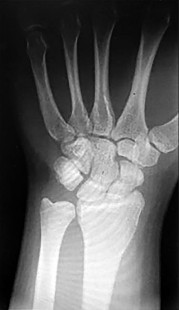

- الأشعة السينية (X-rays): هي الخطوة الأولى في تقييم الكسور، الخلوع، وتغيرات التهاب المفاصل. تساعد في تحديد مدى تدهور العظام والمسافات المفصلية. على سبيل المثال، تُظهر صور الأشعة السينية كسور السلاميات

أو كسور قاعدة العظم المشطي الخامس

، بالإضافة إلى علامات مثل "الدمعة الشعاعية" (Radiographic Teardrop) في الرسغ التي تمثل الزاوية الزندية الراحية الحرجة للكعبرة البعيدة

. - الأشعة المقطعية (CT Scan): توفر صوراً تفصيلية ثلاثية الأبعاد للعظام، وهي مفيدة جداً لتقييم الكسور المعقدة، مثل كسور العظم الخطافي (Hamate Hook Fracture) التي قد لا تظهر في الأشعة السينية العادية

، أو لتقييم مدى تدهور العظم في حالات مثل مرض كينبوك. - التصوير بالرنين المغناطيسي (MRI): ممتاز لتقييم الأنسجة الرخوة مثل الأربطة، الأوتار، الأعصاب، والعضلات. يكشف عن التمزقات،